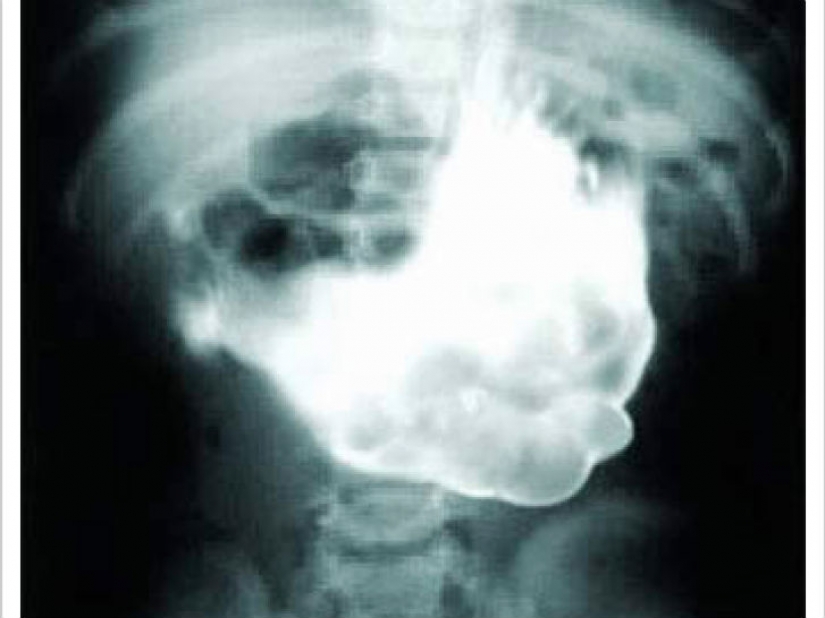

We warned you, don't look if you just sat down to lunch. One 18-year-old girl was removed from the stomach hairball weighing 4.5 kg.